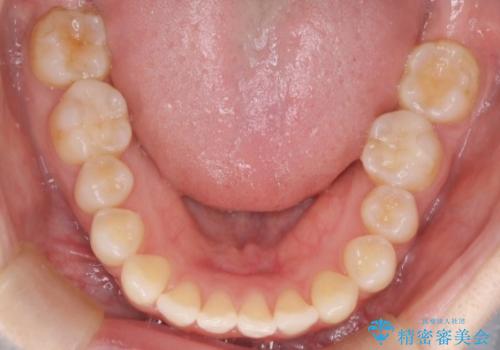

前歯と奥歯のガタガタを矯正で改善

- 患者様は、前歯と奥歯のガタガタ(叢生)を改善し、正面から見た時の歯並びを美しく整えたいとのご要望で来院されました。診断の結果、非抜歯での矯正が可能と判断し、インビザラインを使用する治療計画を立案しました。透明な矯正装置で目立ちにくい治療を行いながら、前歯と奥歯の両方を整列させることを目標にしました。

インビザラインを用いて、前歯の見た目を重視しつつ、奥歯のガタガタも改善しました。特に正面から見た際の美しい歯列を意識し、段階的に歯を移動させることで、全体の調和を図りました。治療中は、適切な装着時間を守ることや、装置の清潔を保つことが重要でした。また、歯肉や歯列全体に無理な負担がかからないように移動を管理しながら治療を進めました。結果として、前歯と奥歯がきれいに並び、見た目にも機能的にも満足いただける仕上がりとなりました。